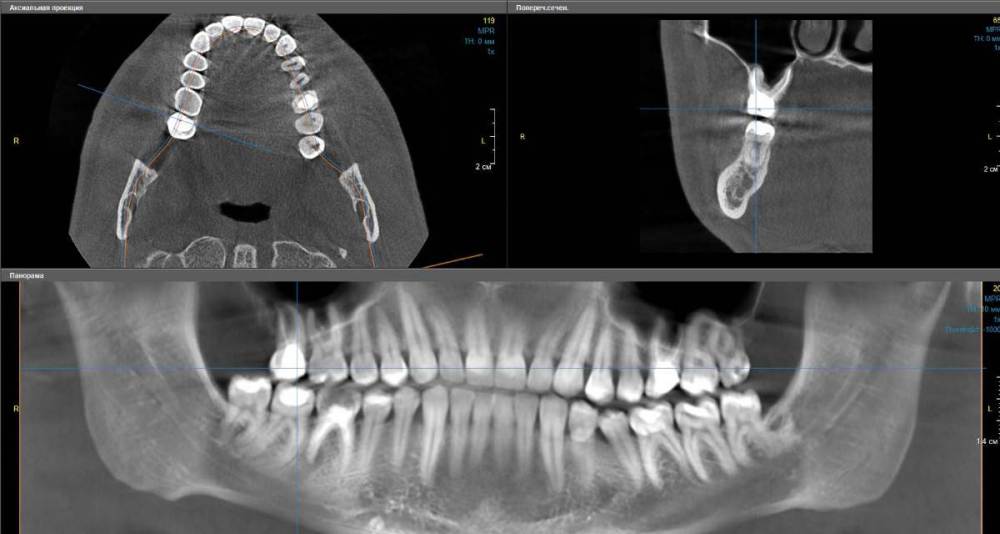

Второй зуб:

Правая верхняя семерка (17), зуб был депульпирован несколько лет назад. Также виднеется маленькая темная полость (см. второй скриншот)

tooth2.jpg